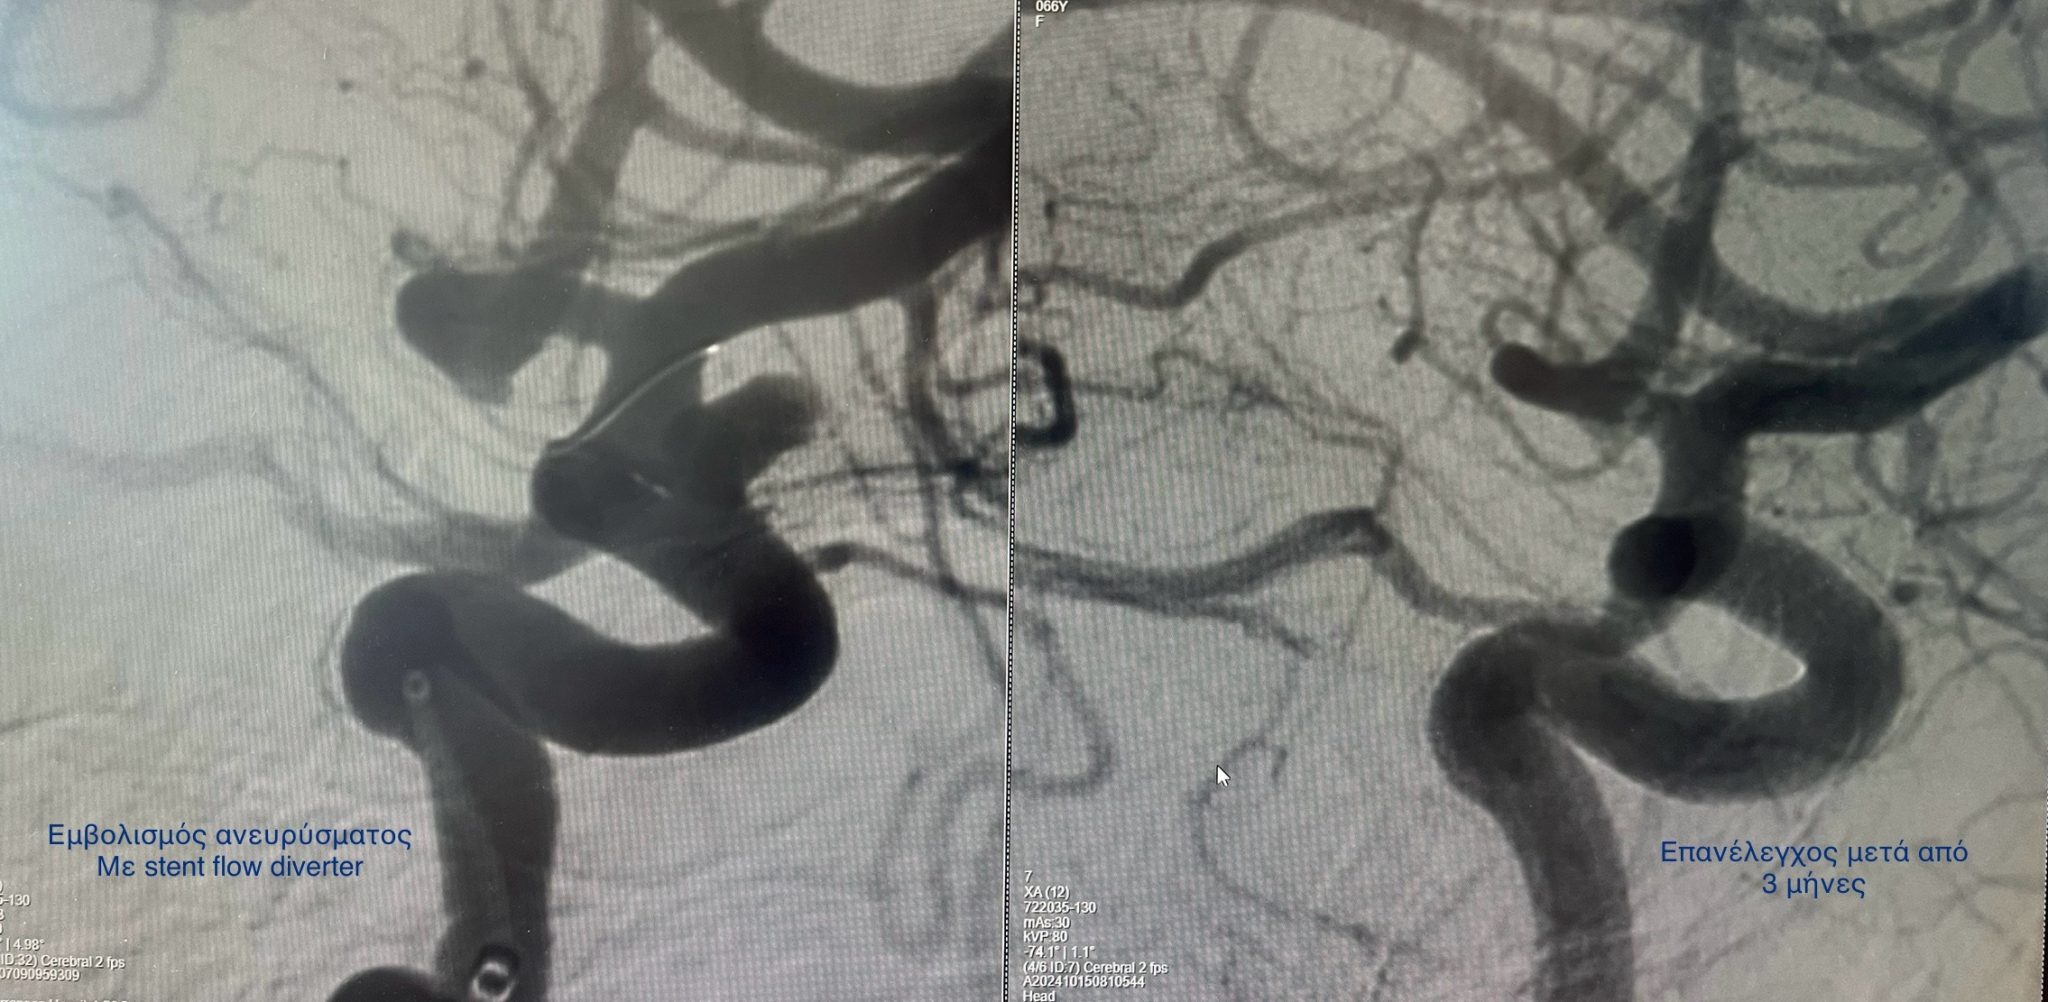

Eμβολισμός ανευρύσματος έσω καρωτίδας με την τεχνική της τροποποίησης της ροής (stent flow diverter)

stent flow diverter

Και η ενδαγγειακή προσεγγίση. Κατά την προσέγγιση αυτή, πλοηγούμε τα υλικά μέσα από τις αρτηρίες και τοποθετούμε μέσα στο ανεύρυσμα μεταλλικά σπειράματα (coils) μόνα ή σε συνδυασμό με ενδοπρόθεση (stent) ή τοποθετούμε ειδική κατηγορία ενδοπρόθεσης (stent) τροποιητή της ροής στην αρτηρία που φέρει το ανεύρυσμα.